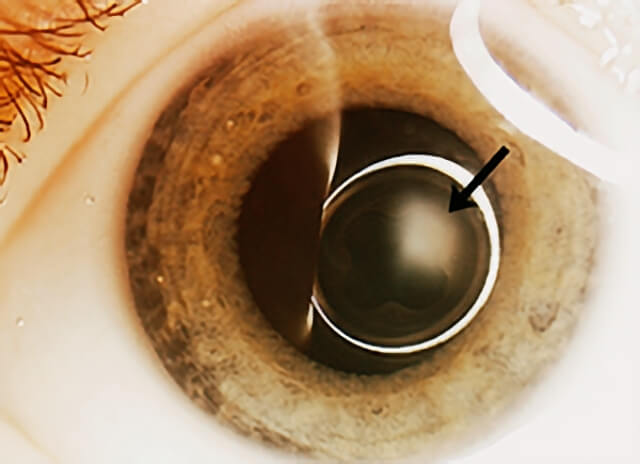

Persistant Fetal Vasculature falls into the group of ocular diseases in infancy characterized by a white pupil—a result of the abnormal tissue behind the lens—termed “leukocoria.”

PFVS falls into the group of ocular diseases in infancy characterized by a white pupil—a result of the abnormal tissue behind the lens—termed “leukocoria.” While the findings of PFVS are typically restricted to the eyes, other conditions with the findings of leukocoria may be life threatening.

The most important disease to rule out when a child presents with leukocoria is retinoblastoma (a rare malignant tumor of the retina). Typically, if one is able to visualize the back of the eye, a stalk is seen spanning the space between the optic nerve and the back of the lens. If the view into the back part of the eye is challenging, ultrasound and/or CT/MRI scans are often performed.